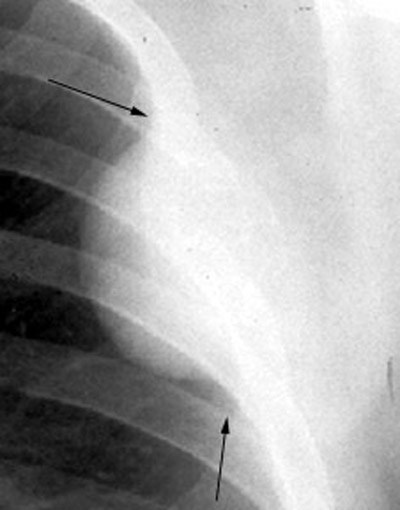

Extrapleural Sign

Expanding lesions of structures in chest wall give rise to this sign. This sign

helps to recognize the site of the lesion. The features of the density are:

- Peripheral location

- Cat under the rug appearance

- Concave

edges

- Sharp inner edge and indistinct outer edge

- Equal length and width in early stages